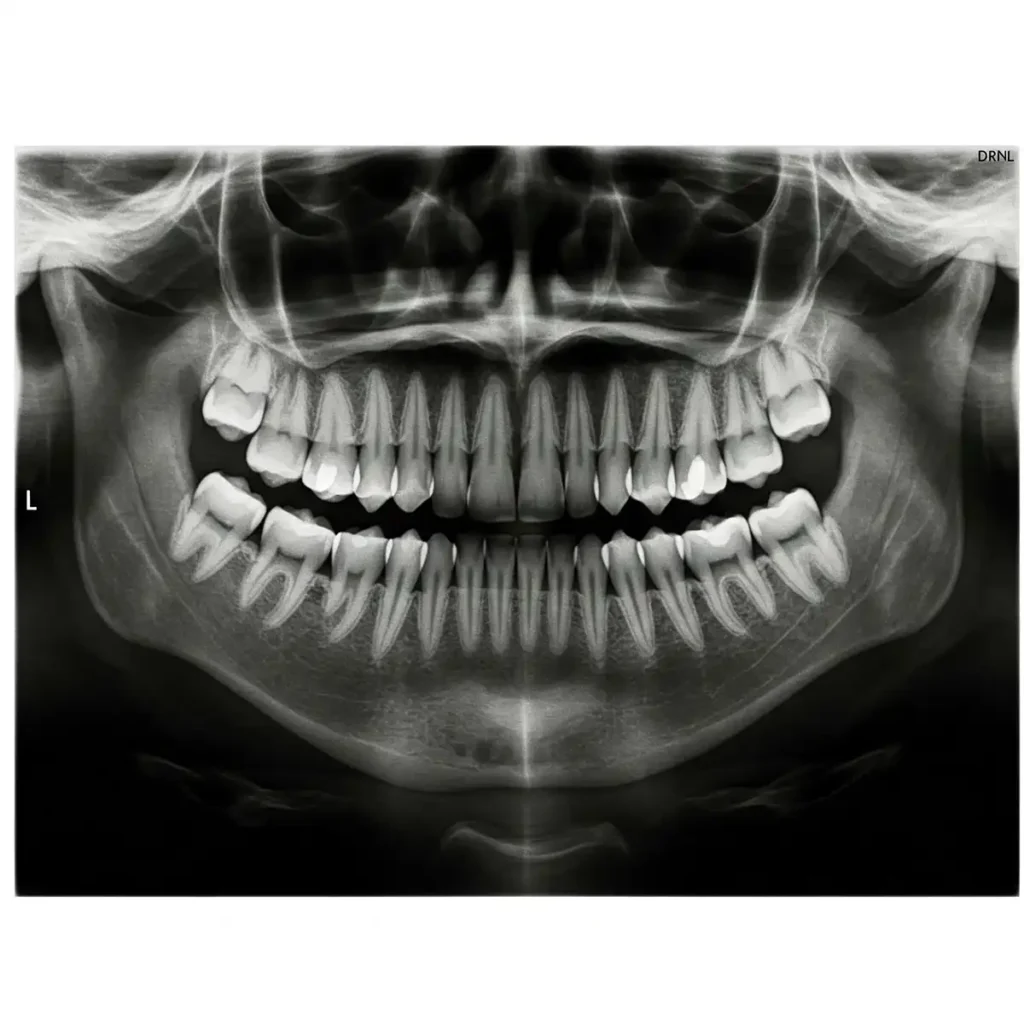

A Panorex (or panoramic) X-ray is a two-dimensional image that captures your entire mouth in one shot. This includes all your teeth, even those that haven’t erupted yet, like wisdom teeth. It also includes.your upper and lower jaws, the temporomandibular joints (TMJ), your nasal area, and even the sinuses.

Unlike traditional intraoral X-rays where a small sensor is placed inside your mouth, the Panorex process is extraoral – the equipment moves around your head while you stand or sit comfortably.

While traditional small digital X-rays provide incredibly fine detail for individual teeth. The Panorex imaging offers a more inclusive view of your entire oral system and surrounding anatomy. Think of it like the difference between looking at a single room through a keyhole (intraoral) versus seeing the entire house from above (Panorex).

This broad perspective is crucial for identifying issues that might not be visible on smaller X-rays, providing essential context for your overall oral health.